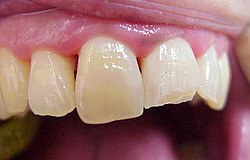

Situation am Patient betrachtet

Die Vitalitätsprobe stellt fest ob ein Zahn nervtot ist. Kältespray wird auf Schaumstoff aufgetragen und an den Zahn gehalten der Zahn lebt wenn der Patient eine Empfindung von leicht kalt bis schmerzhaft berichtet. Nervtest

Wird nichts mehr empfunden so ist er tot und das tote Gewebe muss schnellstens aus dem Zahn entfernt werden (Wurzelkanalreinigung) bevor es im Zahn verfault und zu starken Schmerzen bis hin zur dicken Backe (Zyste) führt. Obwohl im Bild zur Verdeutlichung dargestellt ist eine Aufbereitung des Wurzelkanals (Nervnadel ragt über Wurzel hinaus ) über die Wurzel in den Kieferknochen bei der Zahnwurzelbehandlung natürlich nicht erwünscht. Um dies zu vermeiden müssen während der Wurzelbehandlung Röntgenaufnahmen angefertigt werden, die die ungefähre Länge der Wurzel berechnen lassen. Besser noch lässt sich die Länge der Wurzel elektronisch bestimmen .(Auf Wunsch Privatleistung). Ist die Wurzel an Ihrem Ende weit geöffnet kann es trotz aller Vorsicht zu einem ungewünschten Überaufbereiten und zu einer Überfüllung der Wurzel kommen. Dies beeinträchtigt dann oft den Erfolg. html Text zum Ausdrucken als pdf Datei. Falls über die Wurzelspitze hinaus in den umliegenden Knochen bereits Eiter aufgetreten ist und dieser den Knochen um den Zahn auflöst (das sieht man im Röntgenbild), so muss die infektiöse Wurzelspitze und die darum liegende Zyste entfernt werden .Im Prinzip ähnlich einem Pickel ausdrücken. Sobald der Druck (Eiter) dann heraus kann, geht sehr schnell der Schmerz bzw. auch die dicke Backe zurück. Der Vorgang nennt sich Wurzelresektion oder Apektomie. Die moderne Wurzelbehandlung umfasst Nickel-Titan-Feilen mit drehmomentregulierten Motoren gegen Instrumentenbruch, elektronische Längenmessung, Langzeit-provisorische Wurzelfüllungen mit provisorischen Langzeit-Füllungen. Alles leider Dinge die nicht in der Kassenleistung enthalten sind. So bleiben für den Patienten Kosten von ca. 60-480 EUR (je nach Schwierigkeit ) pro Kanal Aus manchen spezialisierten Prominentenpraxen wurde mir schon von Preisen bis zu 1200 EUR pro Kanal berichtet.